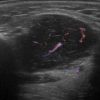

U tuyến nước bọt

» Thông tin: Nam giới – 63 tuổi.

» Lâm sàng: Khối vùng góc hàm.

# Lymphoma tuyến nước bọt dưới hàm.